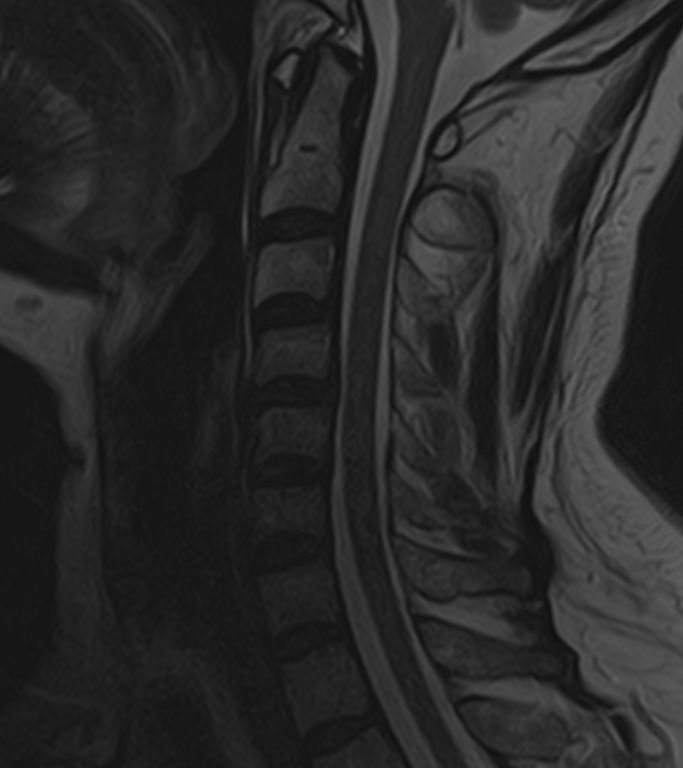

В клинике «Доступная медицина» можно пройти комплексное обследование, включающее в себя два протокола сканирования близко расположенных друг от друга анатомических областей – шейного отдела позвоночника и головного мозга.

Сканирование проводится на современном высокопольном магнитно-резонансном томографе закрытого типа TOSHIBA VANTAGE TITAN 1,5 Тесла, который делает послойные срезы в разных плоскостях с шагом от 1 мм и на основе полученных данных создает трехмерные изображения превосходного качества. Метод исследования позволяет в мельчайших подробностях визуализировать состояние всех структур головного мозга и шейного отдела позвоночника, что дает возможность выявлять патологические изменения на ранних стадиях и назначать своевременное лечение.

Также магнитно-резонансная томография шейного отдела проводится при травмах и падениях, при подозрении на наличие заболеваний позвоночника, а также для подготовки к операции и для контроля эффективности медикаментозного или хирургического лечения.